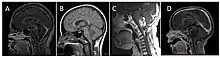

| Brain stem glioma. MRI axial, with contrast | |

Neuroimaging, such as MRI, is the main diagnostic tool for brain stem gliomas. In very rare cases, surgery and biopsy are performed.